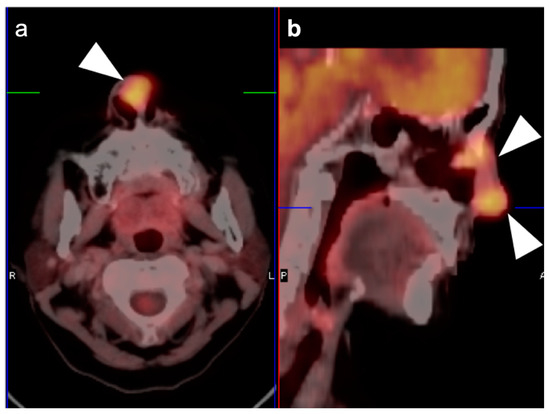

2.2. Squamous Cell Carcinoma of the Head and Neck (SCCHN)

2.3. Nasopharyngeal Carcinoma

2.4. Sinonasal Tumors

2.5. Major and Minor Salivary Gland, Lacrimal Gland Tumors